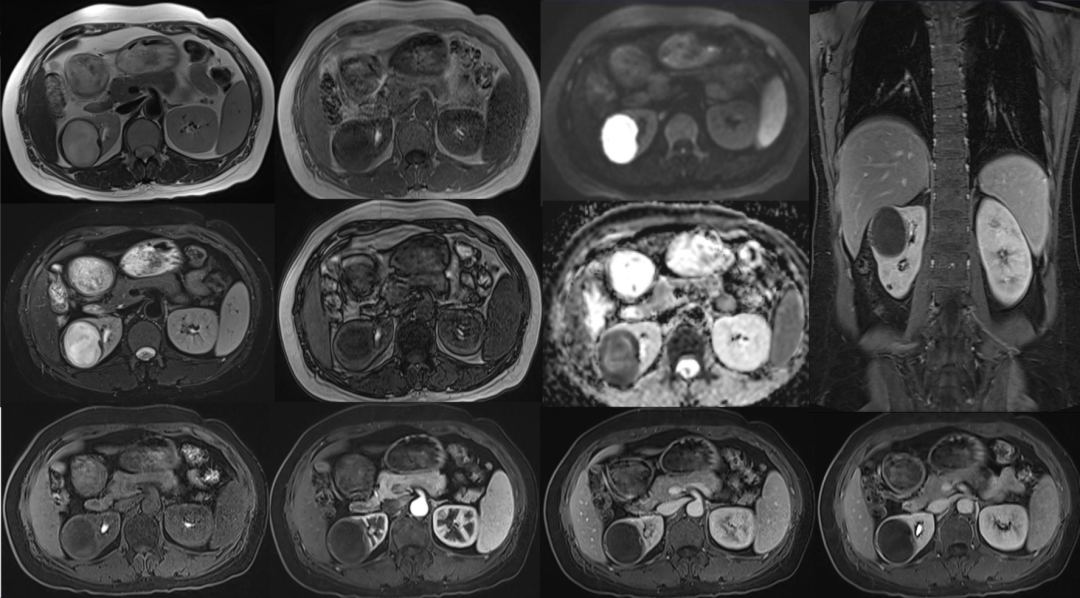

"熊掌征"表现为以肾盂肾盏为中心肾实质内多发囊性占位,其中部分囊为结石梗阻所致的肾积水,部分为黄色肉芽肿的脓腔;通常肾盏扩张为主,肾盂扩张常常不显,增强后,病变实性部分均匀强化,坏死区无强化,低密度区边缘环形强化。患肾体积增大或局限性隆起。常常伴有集合系统结石;肾皮质变薄;肾窦脂肪组织减少,多为慢性炎性反应性纤维组织增生所替代;肾周筋膜增厚、肾周间隙渗出积液,严重时可形成脓肿累及腰大肌。腹部X线平片典型的表现是受累的肾脏增大并有鹿角状结石,同侧腰大肌边缘模糊。超声显示肾脏轮廓变形,正常结构消失,中央可探及结石声影。

影像表现为:右肾囊性肿块,肾周无软组织及渗出影,增强囊壁轻度强化,囊内弥散受限明显,不强化,周围有出血

2.肾脓肿:起病急,发热及泌尿系感染症状明显,无结石或钙化。早期炎症期:表现肾实质内略低密度肿块,增强检查可有轻度不规则强化。脓肿成熟期:表现为类圆形均一低密度病变,增强检查病变周边(脓肿壁)呈环状明显强化,中心脓腔低密度无强化,脓肿内可见液气平面和气泡。感染蔓延期:肾周脂肪密度增高;并有脓肿时,表现肾周和肾旁脂肪间隙消失,代之以混杂密度肿块,增强检查表现为规则或不规则单发或多发环状强化。